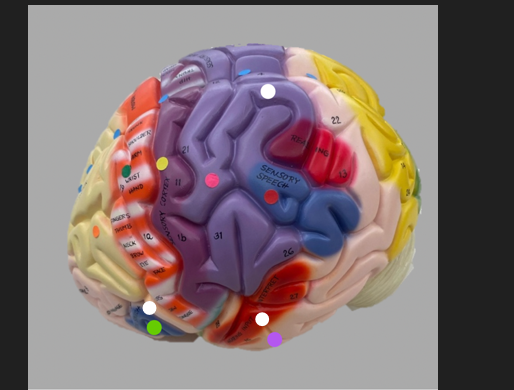

orange dot

frontal lobe

blue dot

longitudinal fissure

dark green dot

precentral gyrus

pink dot

postcentral gyrus

yellow dot

central sulcus

white dot

parietal lobe

light green dot

Broca’s Area

red dot

Wernicke’s Area

orange dot

occipital lobe

blue dot

parieto-occipital sulcus